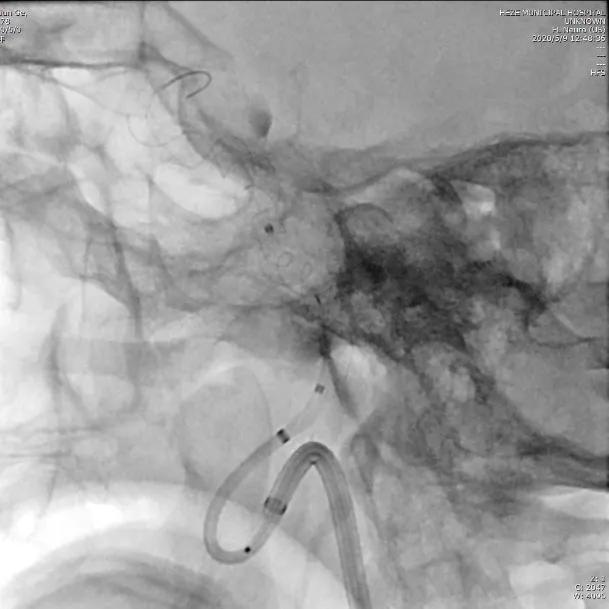

选择5.0×45mm Tubridge®支架,成功释放,覆盖动脉瘤,造影见动脉瘤腔内造影剂明显滞留。